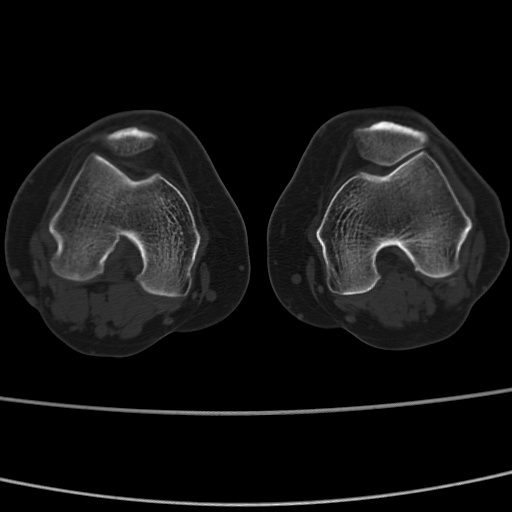

女性,50岁。【请提供患者临床症状体征】

右膝关节退行性改变,关节游离鼠。

右膝关节退行性改变,滑膜黏液囊钙/骨化并游离。